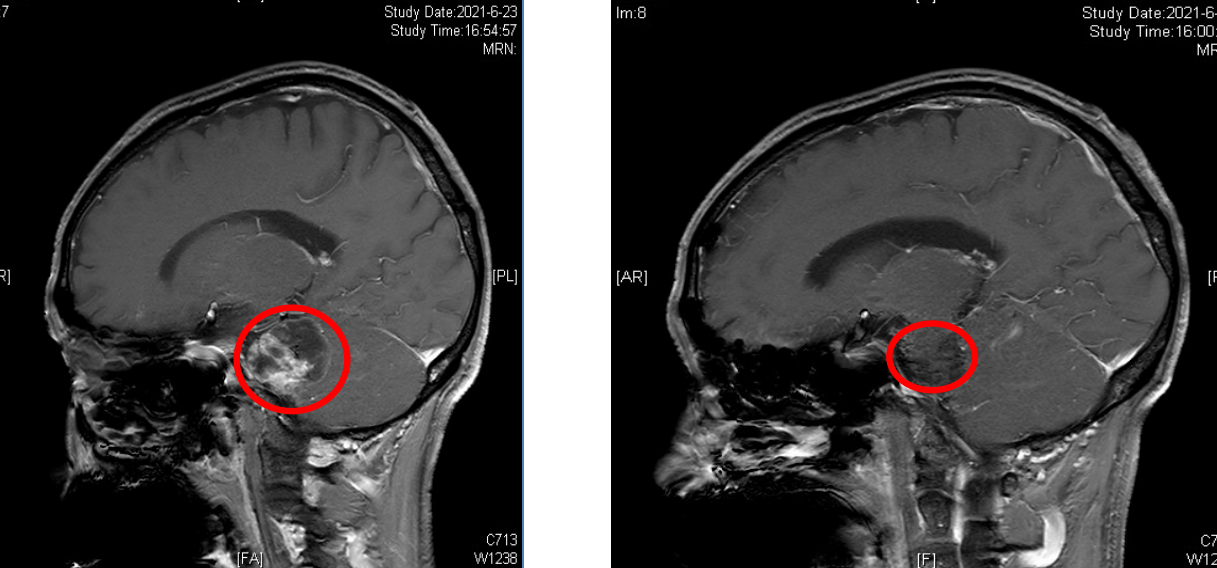

通过头部核磁共振检查显示左侧桥小脑脚区囊实性占位性病灶,大小约4*4cm,是听神经鞘瘤。神经外科副主任、主任医师樊天禹告知患者,听神经瘤属于良性肿瘤,但是会缓慢增长。随着肿瘤的长大,其症状会越来越重,从耳鸣、听力下降直至发展为听力的丧失,甚至压迫周围的神经。因此听神经瘤治疗宜早不宜迟,建议尽早行肿瘤切除手术。

9月10日,长沙市中心医院(南华大学附属长沙中心医院)神经外科手术团队为患者行全麻下颅内肿瘤切除术,术中行面神经电生理监测,手术顺利,术后患者头痛消失,听力及面部麻木好转。

术前与术后对比